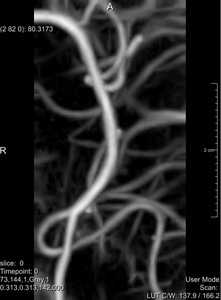

Vessel Enhancing Diffusion

Recently, an implementation of the Vessel Enhancing Diffusion (VED) algorithm [3] using the Insight Toolkit (ITK) framework [2] has been proposed by Enquobahrie et al.[1]. In this paper we present an alternative implementation, for two reasons. First, in this implementation all the main functionality of the algorithm, including eigensystem, vesselness, tensor calculation and PDE discretization using a forward Euler scheme are now grouped together in one single class. Although this may come at the cost of code-reusability, it improves readibility and enables application specific code optimization. The second reason is the criterion of reproducibility. Source code, test environment and example data of the paper [3] are provided.